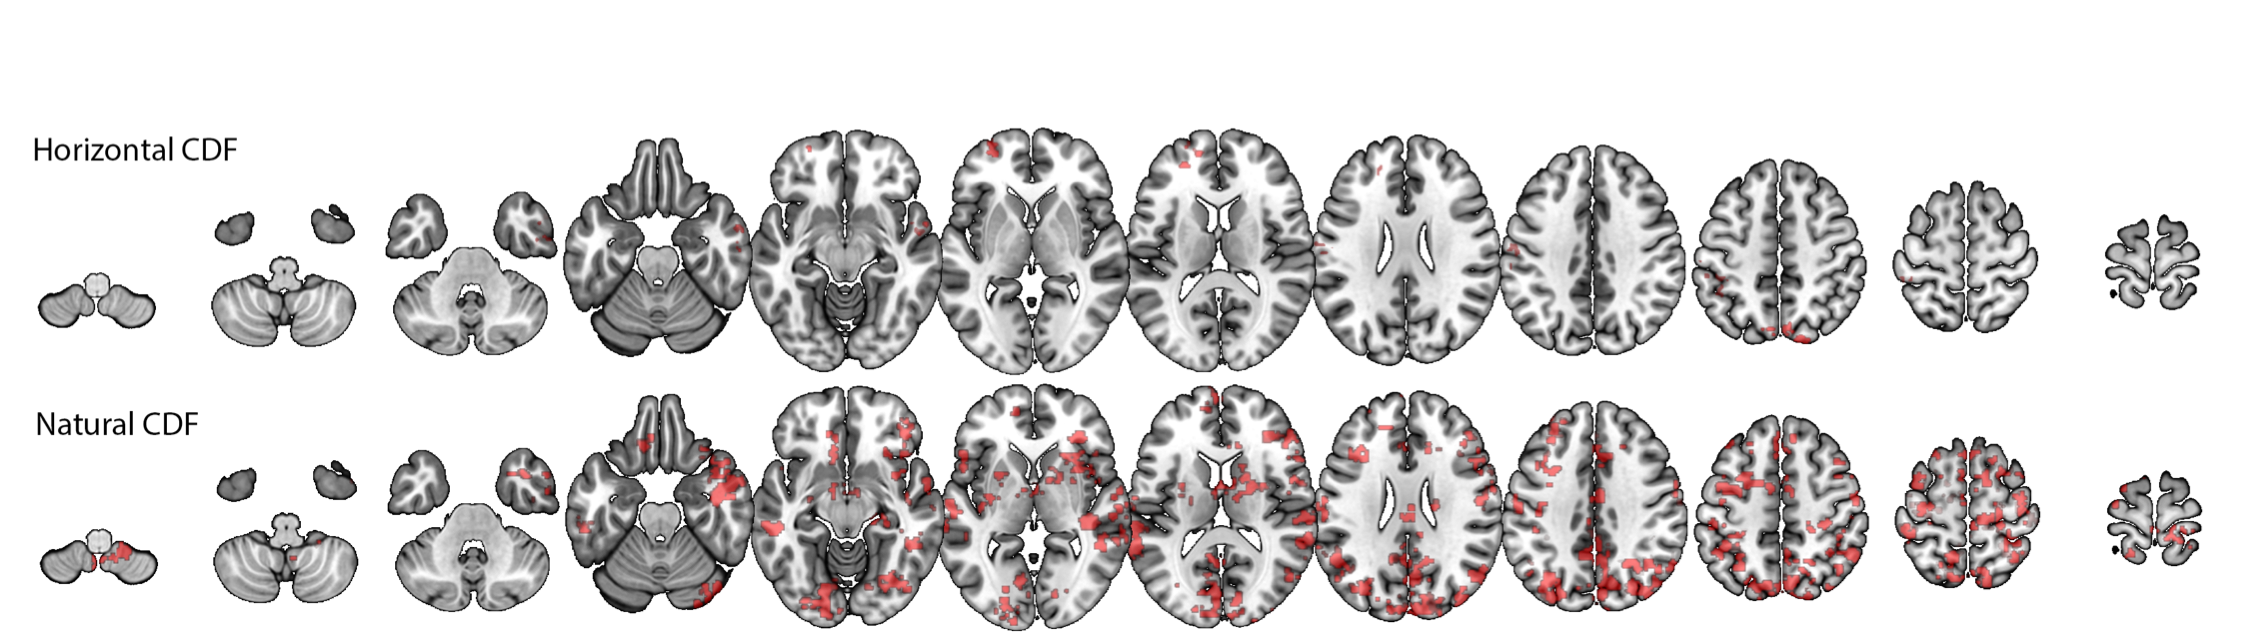

Single-voxel calculations, and group-level analyses. The sleep-staging procedure allowed us to obtain fMRI time series for wakefulness (W) and three different sleep stages: N1, N2 and N3. On the single participant level, for each of the four conditions, we conducted voxel-wise analyses to derive the node-degree histograms for the top and bottom graphs (i.e. these were derived for each voxel). These were represented as the empirical cumulative distribution function. With these CDFs we could answer the following two questions:

On the group level, to evaluate voxels showing statistically-significant AoVH within each study condition (W, N1, N2, N3) we conducted voxel-wise repeated measures ANOVA with two fixed factors; Time series view (two levels [Top, Bot]), and node-degree-histogram Bin (8 levels as explained above). To enable inferences about the population, we modeled participants as a random factor. In order to compare between any two conditions (e.g., W vs. N1) we derived the AoVH for each condition, and conducted a repeated measures ANOVA with 2 fixed factors: Condition (e.g., W vs. N1) and Node degree histogram bin of the difference histogram (8 bins, values 2(min)-9(max)). We note that 8 bins are used here, as the 9th bin would not be independent of the prior 8 (due to normalization).

These analyses returned a statistical significance value for the interaction term, for each brain voxel. We then implemented a clustering procedure forman99 to identify brain areas where many contiguous voxels, each with a value of .001 show a significant interaction: this identifies an ‘activation cluster’.

IV.1 Application to fMRI

We first compared the top and bottom visibility graphs within the Wakefulness and the three sleep stages (N1, N2 and N3). As shown in Figure 5, we found significant differences, predominantly in thalamic and frontal regions, for each of these conditions, with the exception of the case of VG in the N3 sleep condition.

To better understand these results, we determined which visibility values tended to contribute most strongly to the statistically-significant differences in degree distributions that produced the Wakefulness (W) results in Figure 5 (rows 1, 2). To this end, for each cluster we derived a histogram that communicated the visibility bins that most strongly differentiated the top and down degree distributions for each voxel in the cluster. We did this by (i) transforming the cluster to original space, (ii) for each voxel, identifying the bin that maximally differentiated the top from down histogram, (iii) transforming that value to common space, (iv) creating an average across participants for each voxel in the cluster. The resulting histograms communicated a very clear and consistent result: for VG the modal degree value that maximally differentiated the top and bottom histograms was 4, with narrow tails towards the values of 3 and 5 (indicating that for some participants, some voxels maximally differentiated the histograms at values 3 and 5). Importantly, there were no cases with means below 3 or above 5. For HVGs, in all clusters the modal degree value that maximally differentiated the top and bottom histograms was 3, with very narrow tails towards 2 and 4.

These findings are very important as they show that the differences identified by VGA (AoVH) were driven by very local dynamics rather than due to differences in propensity of isolated extreme events.

In a separate analysis, we also found that VGA profiles could discriminate wakefulness from sleep. As shown in Fig.6, we identified numerous areas, in both occipital (visual cortex) and lateral temporal cortices, where dynamics during wakefulness and N2 sleep differed significantly. No differences were found between W and N1 or between W and N3.

In applying this method, we first found that it offered a new view into spontaneous resting state dynamics in the human brain. While prior neuroimaging work based on amplitude-variance-asymmetry had pointed to sensory cortices as ones having different peak vs. pit dynamics AVA , the current results identify frontal regions as exhibiting asymmetric resting-state BOLD fluctuations during wakeful rest. Furthermore, these asymmetric patterns were also found during the deeper sleep stages (N2 and N3), which is a departure from prior findings (DAVIS16) where AVA failed to identify such signatures. An important result was that in all clusters, these dynamics were driven by differences in the relative frequency of time points (nodes) with relatively low degree, indicating that these differences are not due to a difference in relative frequency of rare, extreme events but due to differences in frequency of time points with relatively moderate connectivity – i.e., a very local phenomenon.